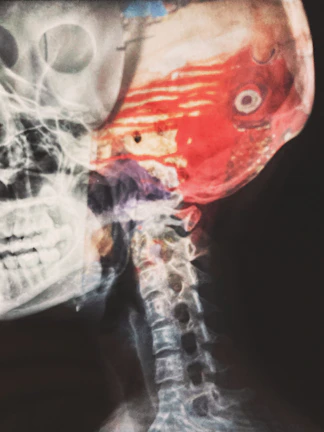

Mielopatia Cervical

Compressão da medula é uma condição séria.

Quanto antes tratar, maiores as chances de preservar função neurológica.